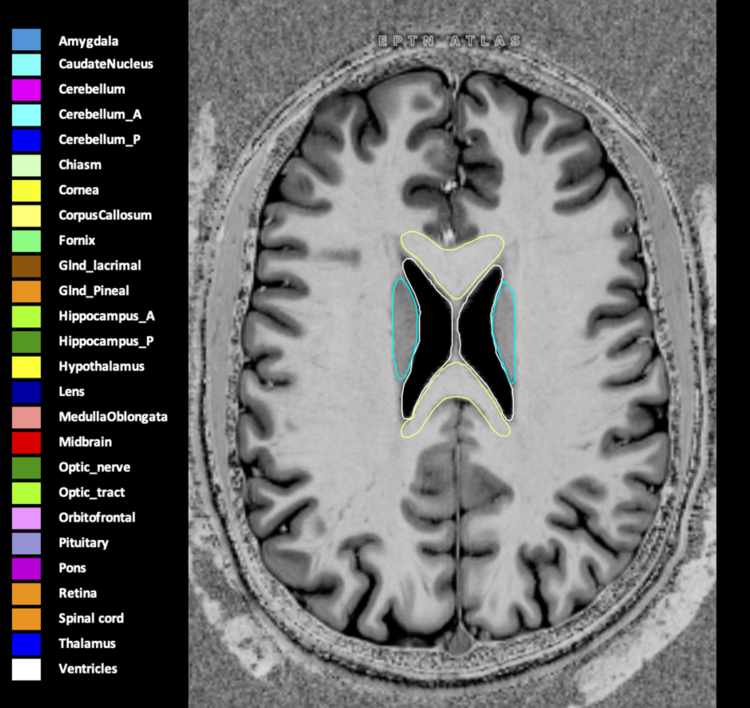

Included are all OARs known to be relevant for radiation-induced toxicity in neuro-oncology: brain, brainstem (midbrain, pons, medulla oblongata), chiasm, cerebellum (anterior & posterior), cochlea, cornea, hippocampus (anterior & posterior), hypothalamus, lens, lacrimal gland, optic nerve, pituitary, skin, and vestibular & semicircular canals. To further facilitate research on cognition, vision and radiological changes after irradiation of the brain, potential clinically-relevant OARs are included: amygdala, caudate nucleus, cerebellum (anterior & posterior), corpus callosum, fornix, macula, optic tract, orbitofrontal cortex, periventricular space (PVS), pineal gland, and thalamus.

Three-dimensional delineation of the 25 consensus OARs for neuro-oncology are shown on CT (WW/WL 120/40, 3000/600), 3T MR images, (T1Gd, T2FLAIR 1mm) and 7T MR (MP2RAGE 0.7 mm). All are presented in transversal, sagittal and coronal view.